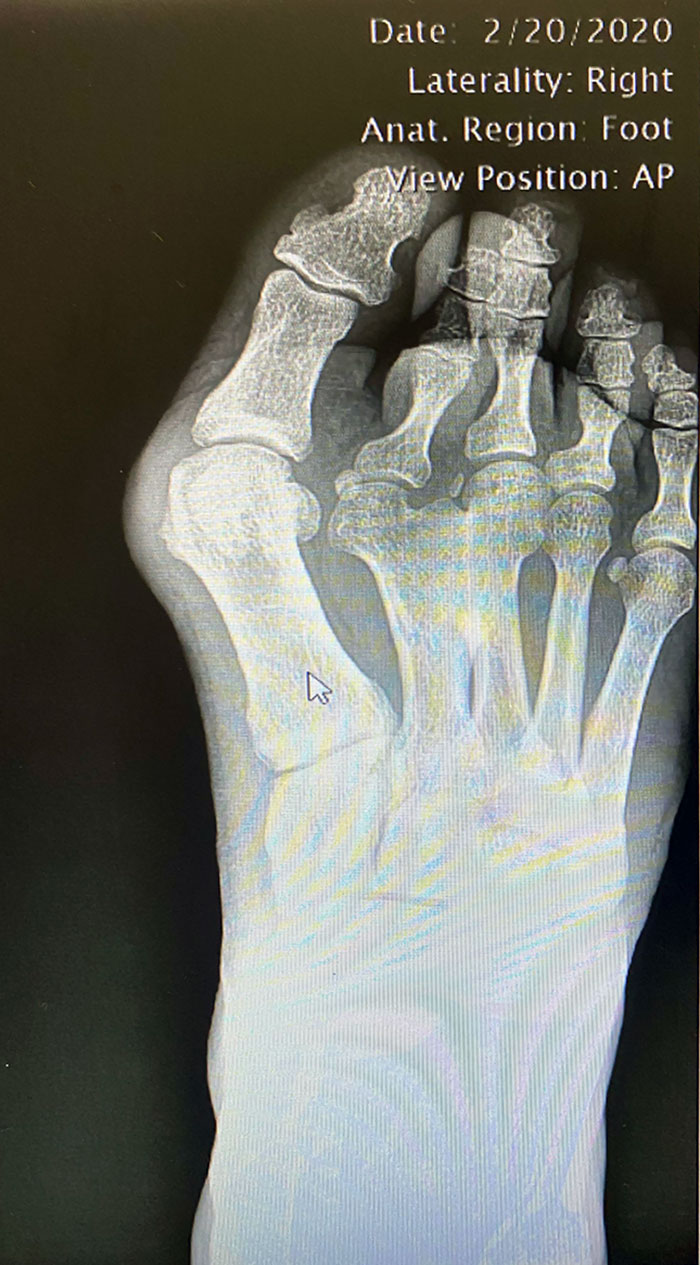

Advanced Rheumatoid Arthritis

My daughter was diagnosed with RA when she was 13. She is 29 now and has had three surgeries to improve her joints to help her be able to walk. Her toes looked much like this X-ray. This is a horrible illness that is invisible until it is at this point. The pain that these patients deal with every day is heartbreaking. People still give her dirty looks when she uses a handicap parking space. Imagine if your toes looked like this...don't you think you would want to walk as little as possible?

The Worst Case Of Rheumatoid Arthritis I've Ever Seen

X-Ray Of My Bunion. I Thought It Was Interesting

the most interesting bit isn't the bunion but how two of her foot bones have fused together